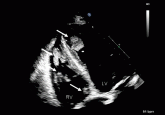

ArticleMultiple intracardiac thrombiAuthor:Nabil S. Zeineh, MDPublish date: July 1, 2013A 60-year-old woman presents with massive venous thrombosis. What is the cause?Read More